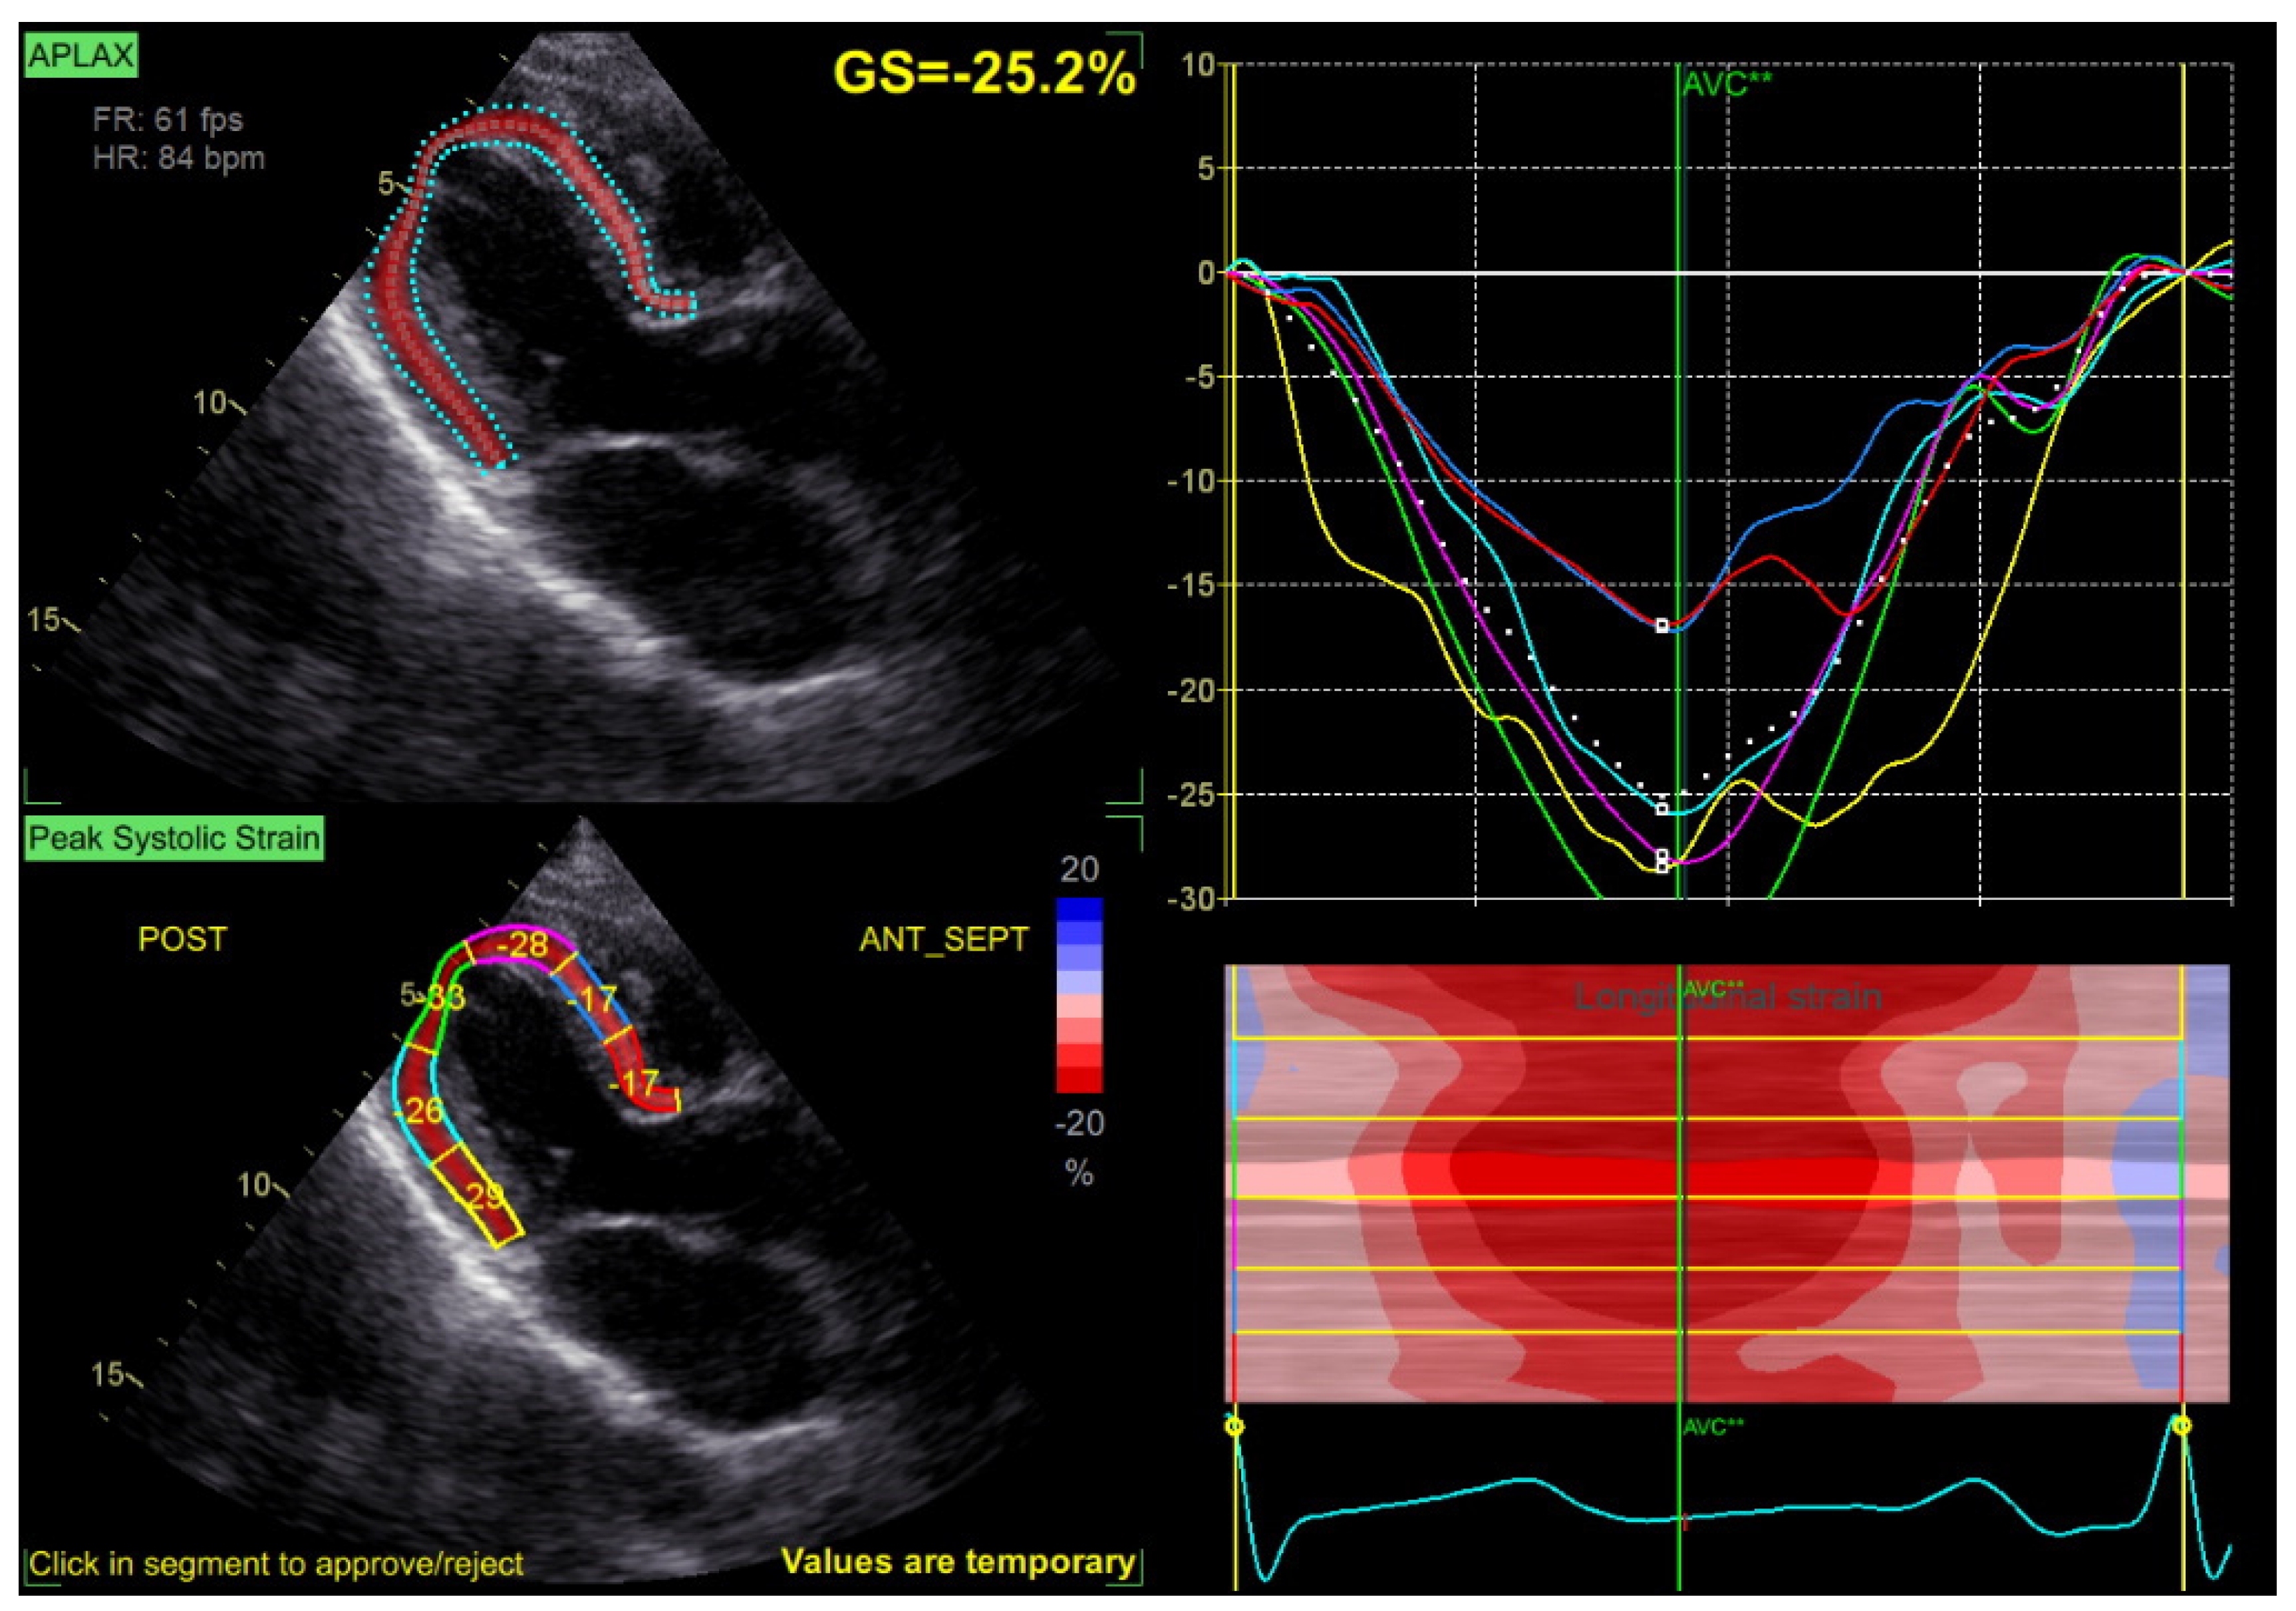

3.2. GLS at Baseline and during Follow-Up

| LVS GLS, % | 22. 3 ± 2.1 | 19.5 ± 3.1 | 19.1 ± 3.7 | 0.024/0.019 |